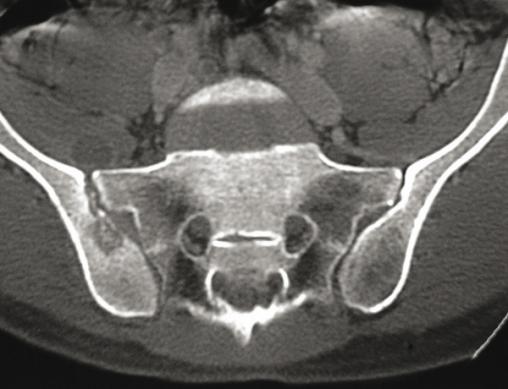

Tomodensitométrie des articulations sacroiliaques montrant une sacro-iliite tuberculeuse droite. Effacement de l'os sous-chondral, séquestres, petite collection abcédée en regard de l'interligne.